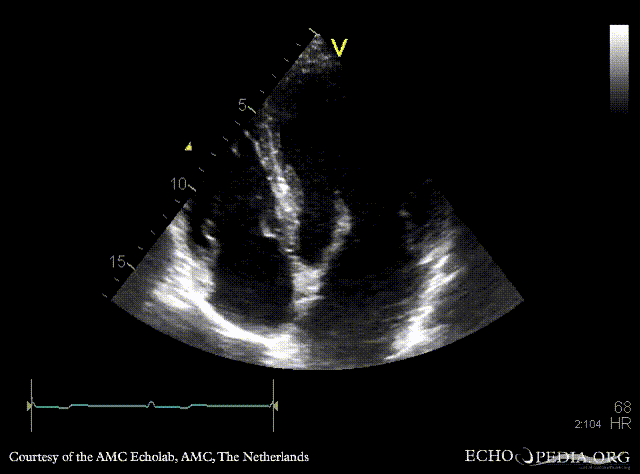

| A3CH